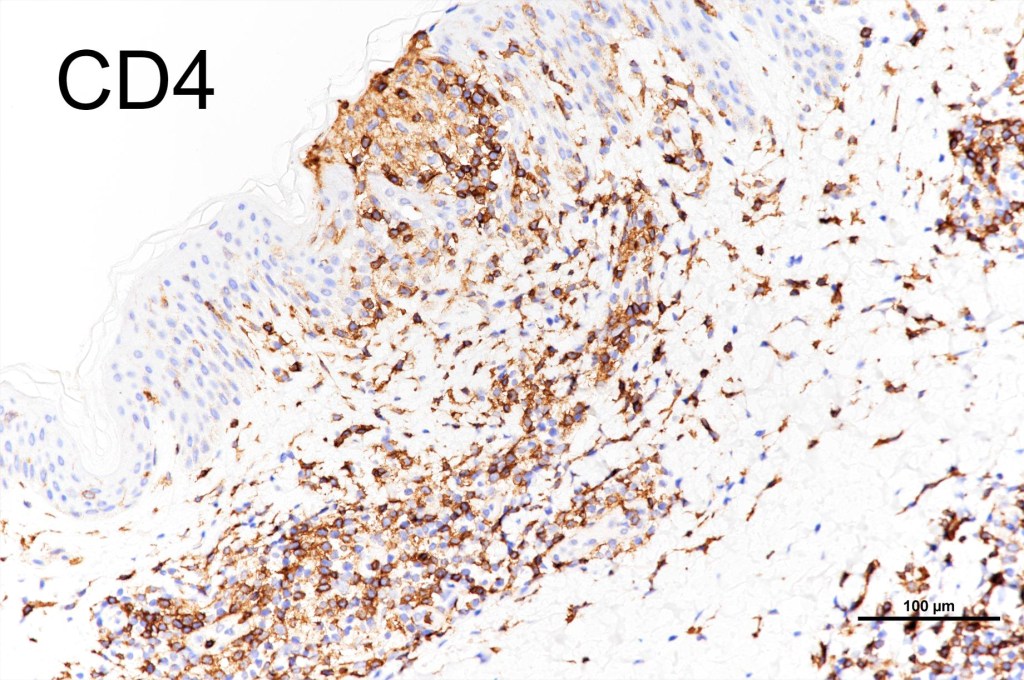

•CD4, CLA, MUM1 +ve